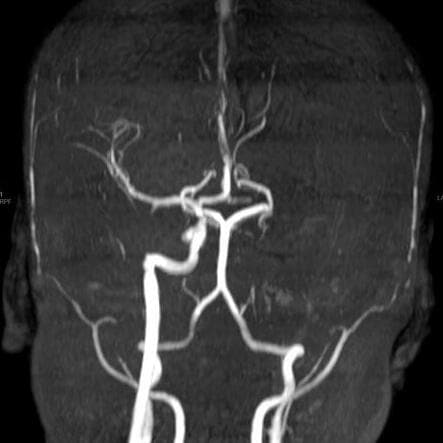

העורק במוח של ש' לפני ואחרי שפתחו את החסימה שהייתה בו כתוצאה מהגידול

צוות מצנתרים, בראשות ד"ר ולדימיר בורודצקי, מצנתר מוח בכיר ביחידה, ביצעו צנתור מוח מורכב בהרדמה מלאה שארך יותר מארבע שעות. במהלך הצנתור המורכב התברר שעורק התרדמה הפנימי משמאל חסום ממוצאו. החסימה הייתה עקשנית ולא ניתנת לפתיחה בדרכים המקובלות בצנתורי שבץ. לבסוף הוחלט על השתלת תומכן (סטנט) באזור החסימה בעורק במוח, מה שאפשר הוצאת חלקי קרישי דם ופתיחת החסימה.